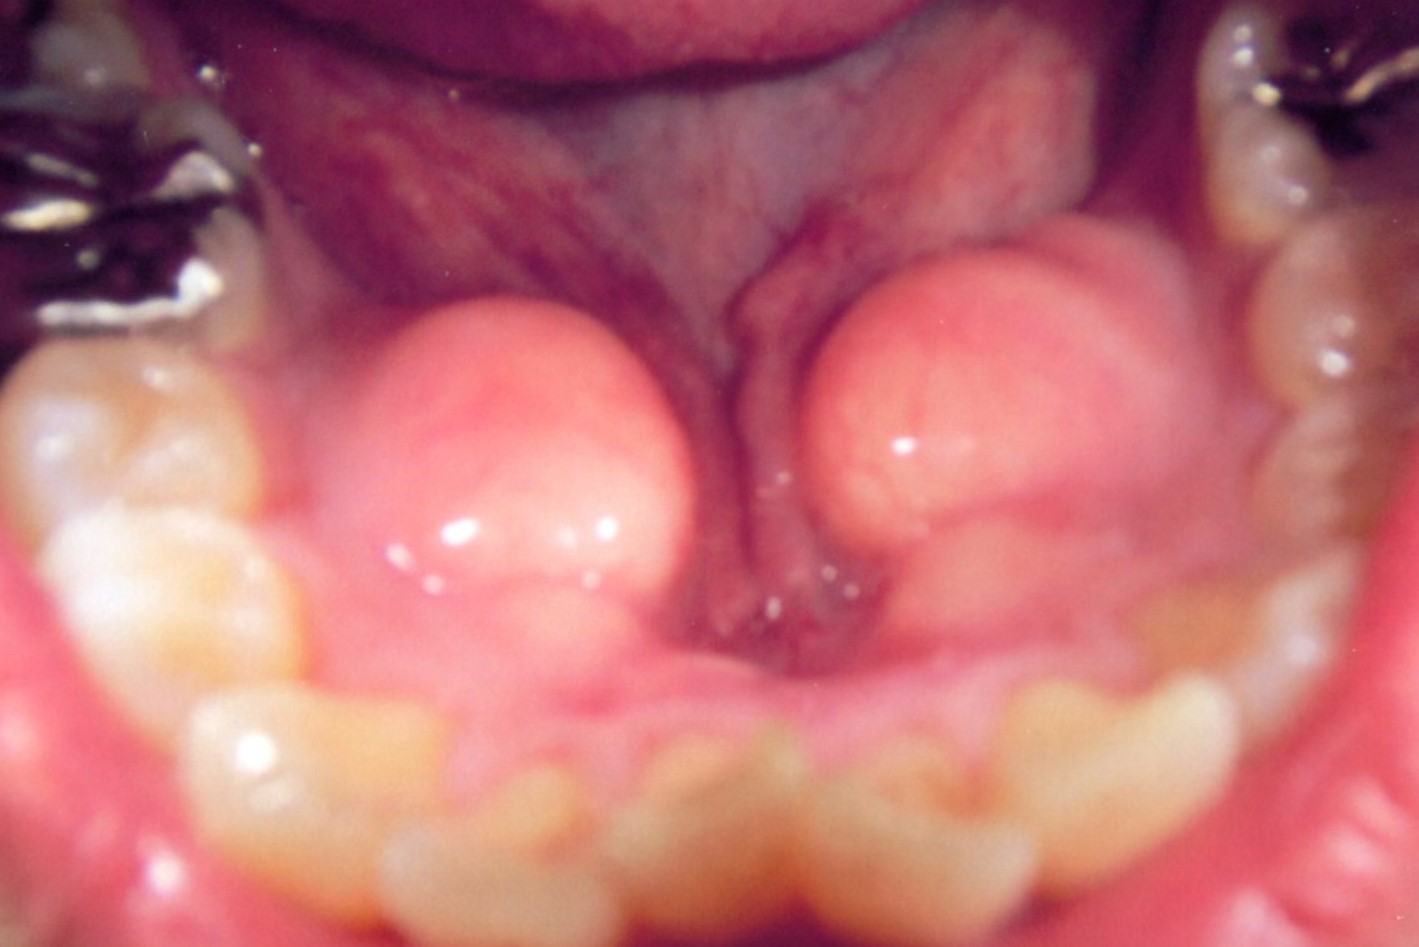

(2)下顎隆起 torus mandibularis

(1)下顎隆起

過剰な下顎隆起は義歯の製作、着脱などに大きな支障となります。

その様な場合、下顎隆起形成術が必要となります。

局所麻酔下に20分ほどで終わり、術後の痛みも余りありません。